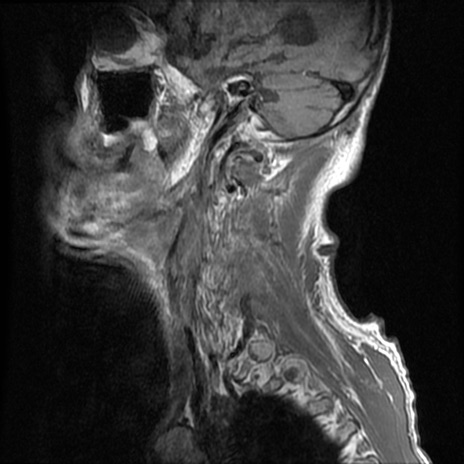

症例46 頚椎MRI T1WI(矢状断像)

頚椎MRI

T2WI(矢状断像)